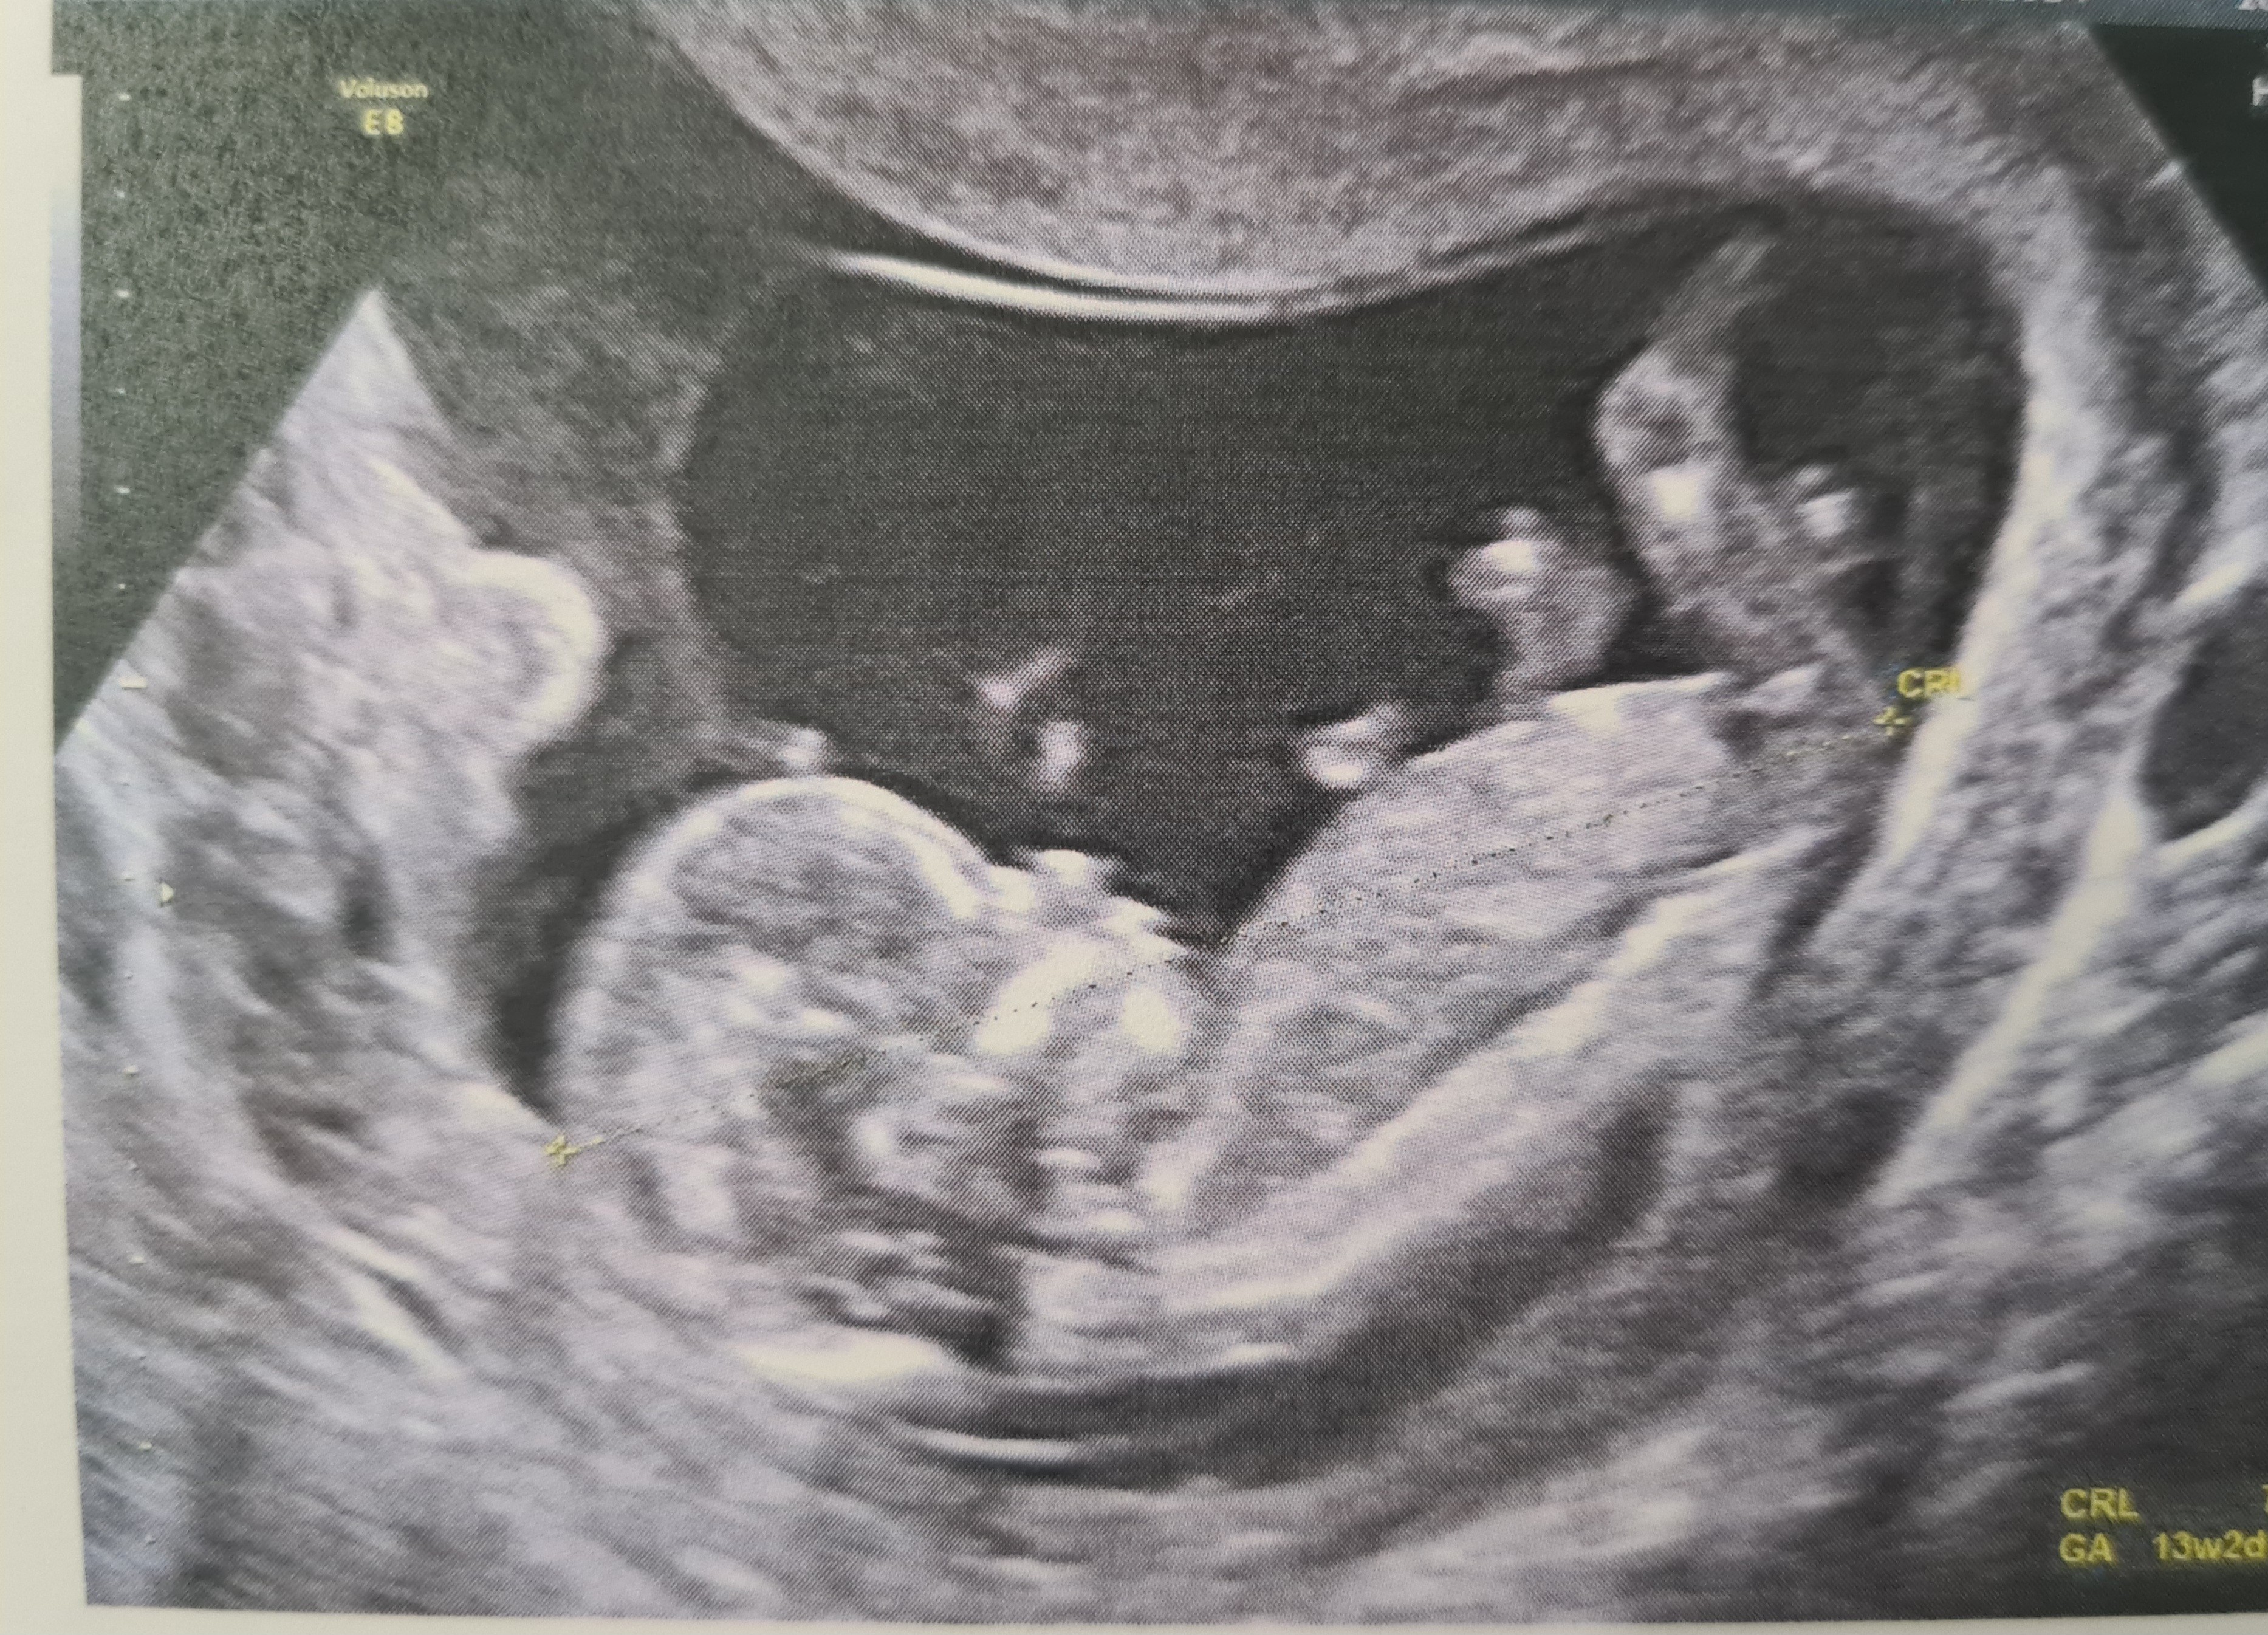

Cześć dziewczyny, zaczynam dzisiaj 17 tydzień. Wczoraj mialam usg i nadal nie znamy płci :( Czy możecie pomóc? :) Co myślicie po zdjęciach z badań prenatalnych? :) Na badaniach dowiedzieliśmy, że płeć do potwierdzenia na kolejnych :/

Z zamieszczonych zdjęć niestety nie da się ocenić, ale jak bardzo wam zależy na szybkim poznaniu płci to polecam NIFTY lub saco, można poznać już nawet w 10 tygodniu.

A na zdjęciach niestety ale faktycznie nie da się w 100% określić płci. Bywa i tak.